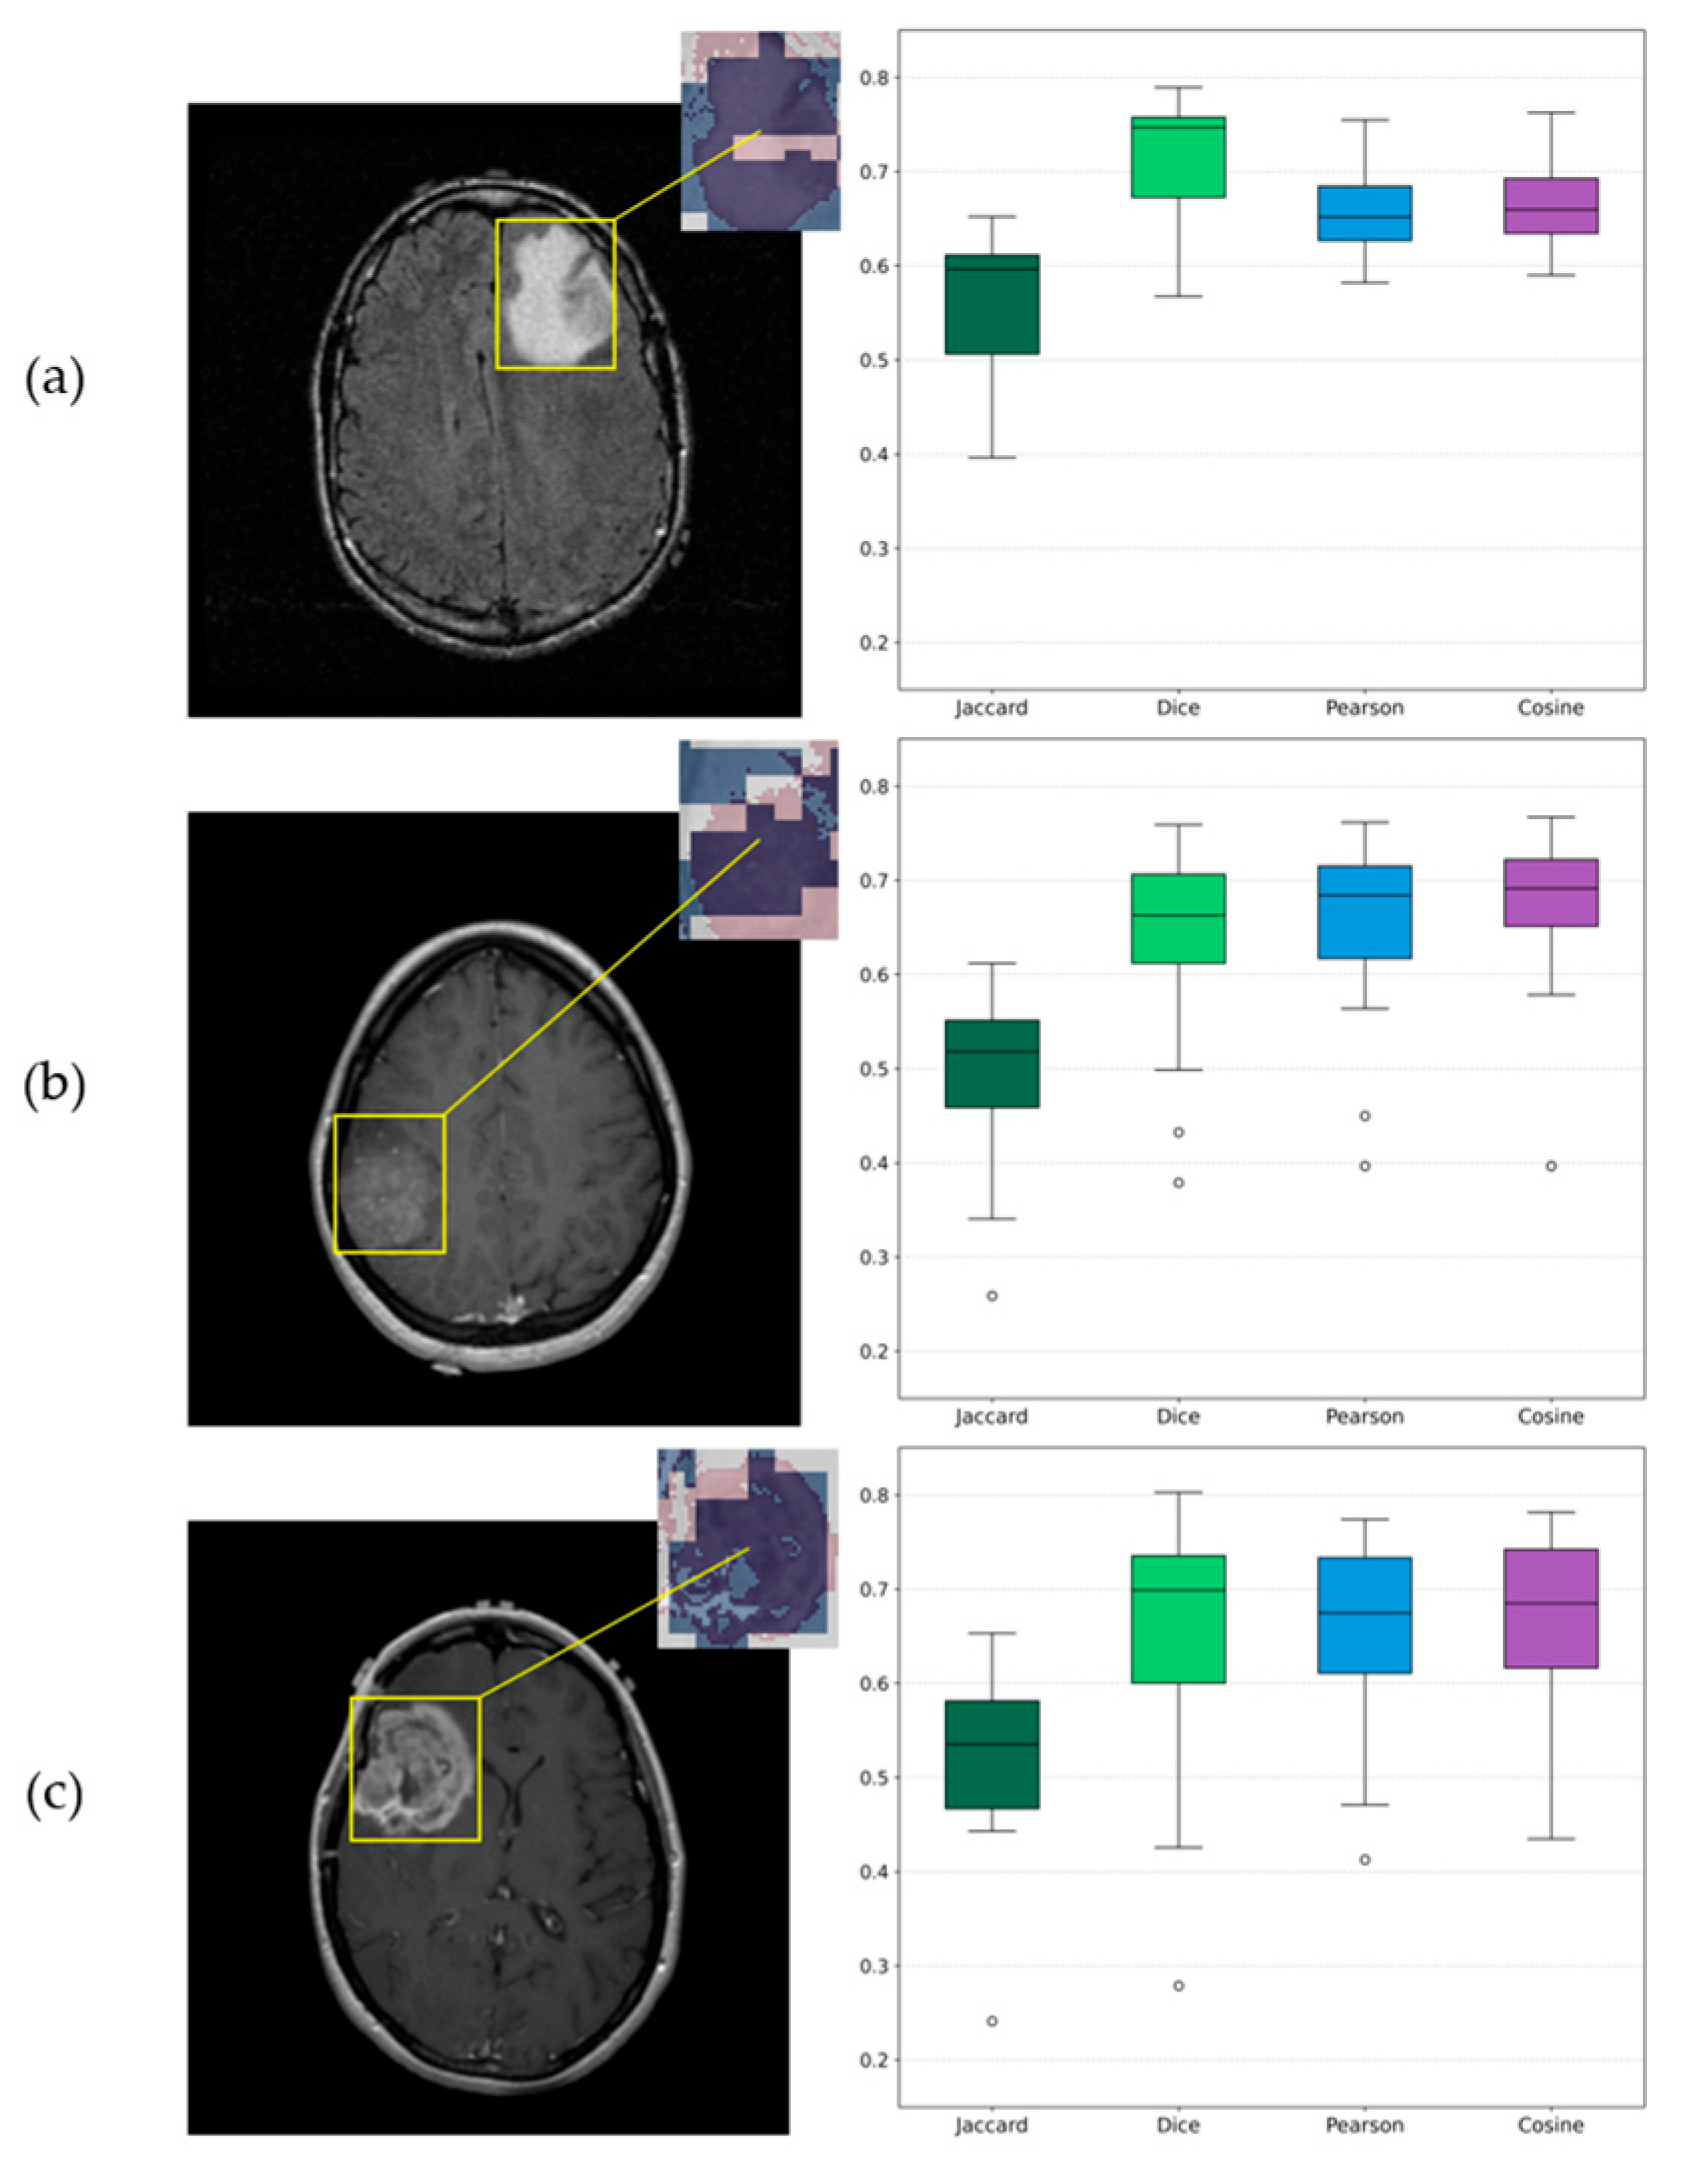

Beside the visualizations that provide a qualitative perspective for assessing each algorithm’s results, a quantitative analysis was conducted to examine their agreement across the 12 independent runs. The outcomes of this evaluation are summarized in Table 7, which presents the average similarity metrics along with the corresponding sample-based standard deviations between SHAP and LIME within the tumor regions. Additionally, a representative visualization of the mean overlay for the three examples is presented in Figure 16. From left to right, each row shows the original slice with the corresponding ROI, a zoomed-in view of the same ROI with SHAP and LIME mean maps overlaid in the red and blue channels, respectively, and boxplots derived from the similarity metrics, providing a visual representation of their distribution across experiments.

Explainable AI (X-AI) methods were also integrated into the study to enhance transparency and interpretability. Both SHAP and LIME algorithms provided visual explanations, highlighting common regions of high importance across samples. The subsequent similarity analysis further quantified this agreement, showing that the models were largely consistent, with all mean Jaccard values above 0.5 and Dice, Pearson and Cosine metrics above 0.6, despite the presence of two outlier runs. This outcome is reasonable given the different mechanisms of the two algorithms. Overall, this agreement confirms that the model’s predictions were based on meaningful tumor-related regions and demonstrates its ability to accurately identify and intergrade these critical areas into decision-making process.

Figure 16. Visualizations of similarity analysis results between SHAP and LIME algorithms for (a) Grade 2 astrocytoma sample; (b) Grade 3 astrocytoma; (c) Grade 4 astrocytoma. From left to right, the ROI is highlighted on the corresponding original slice, a zoomed-in ROI view of SHAP and LIME mean maps overlaid in red and blue, respectively, and the corresponding boxplots provide a visualization of distributions.

Table 7. Similarity metrics between SHAP and LIME maps within the ROIs across runs of the Proposed CNN. Values reported as mean ± standard deviation, with the corresponding 95% C.I. shown in brackets.

SampleJaccardDicePearsonCosine

Grade 20.56 ± 0.08 [0.51–0.61]0.72 ± 0.07 [0.68–0.76]0.66 ± 0.05 [0.63–0.69]0.67 ± 0.05 [0.64–0.70]

Grade 30.50 ± 0.10 [0.44–0.56]0.63 ± 0.11 [0.56–0.70]0.64 ± 0.11 [0.57–0.71]0.65 ± 0.12 [0.57–0.73]

Grade 40.51 ± 0.10 [0.45–0.57]0.64 ± 0.14 [0.55–0.73]0.65 ± 0.10 [0.59–0.71]0.66 ± 0.11 [0.59–0.73]